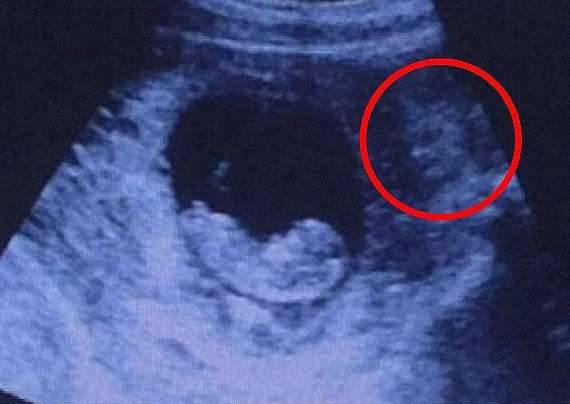

▼超音波照片经常会出现有趣的画面,之前就有人发现一个恶魔正在看自己刚刚一个月大的宝宝。